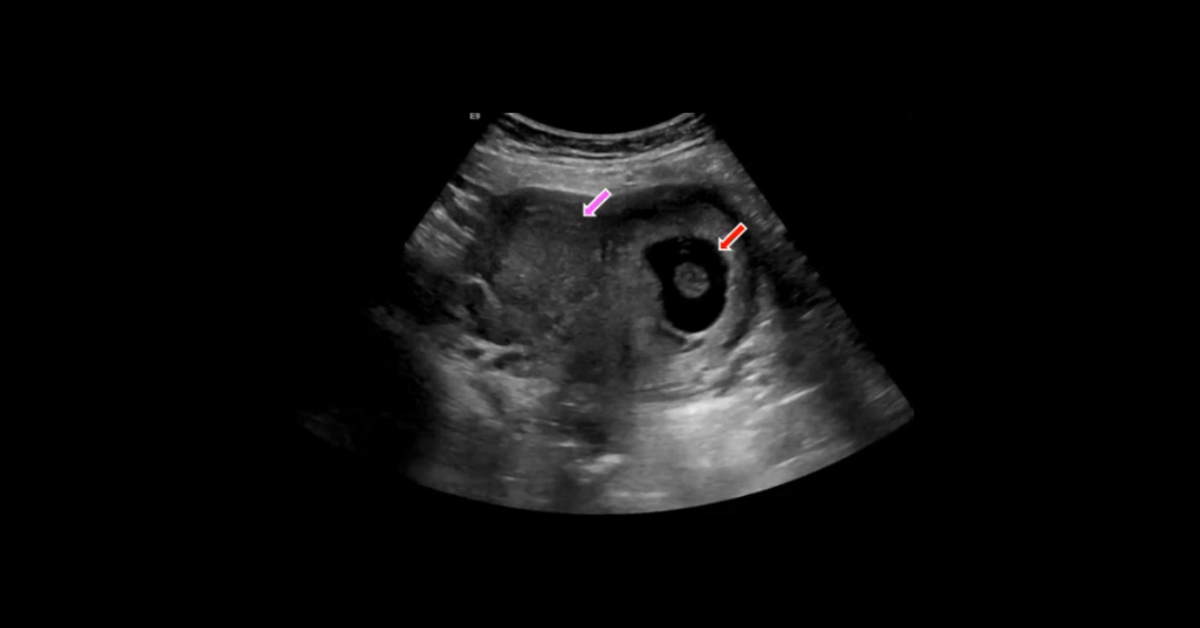

A collection of early pregnancy ultrasound studies presented in cine and screen shot formats, with initial presentation of each case enabling participants to render their own diagnoses followed by detailed discussion of each case.

1. Describe the typical US findings in a variety of early pregnancy abnormalities.

2. Understand the locations of abnormal gestational sac implantation.

3. List the suggestive secondary findings in ectopic pregnancy.